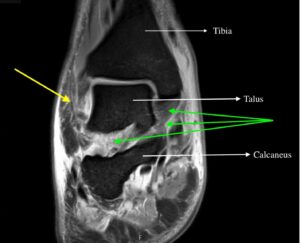

Septic Arthritis. Ankle MRI Coronal. Annotated. JETem 2024